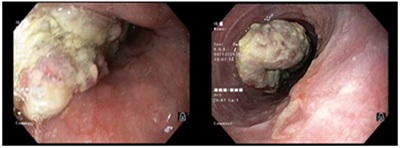

UNG THƯ DẠ DÀY KHỞI PHÁT SỚM

Theo Globocan 2022, ung thư dạ dày đứng thứ 5 về tỷ lệ mắc và tỷ lệ tử vong, với 968 784 ca mắc mới và 660 175 ca tử vong. Bệnh tiến triển thầm lặng, các triệu chứng ban đầu  thường mơ hồ và không đặc hiệu dễ nhầm lẫn với các bệnh lành...